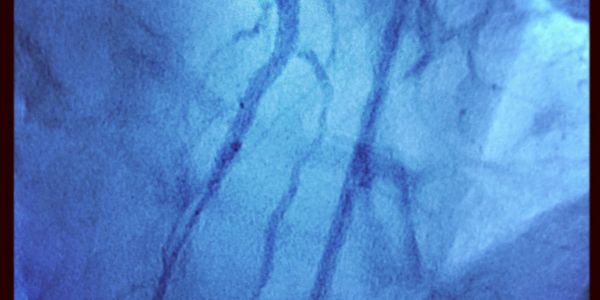

Atención integral del corazón, arritmias, infarto, insuficiencia cardíaca y estudios de alta especialidad